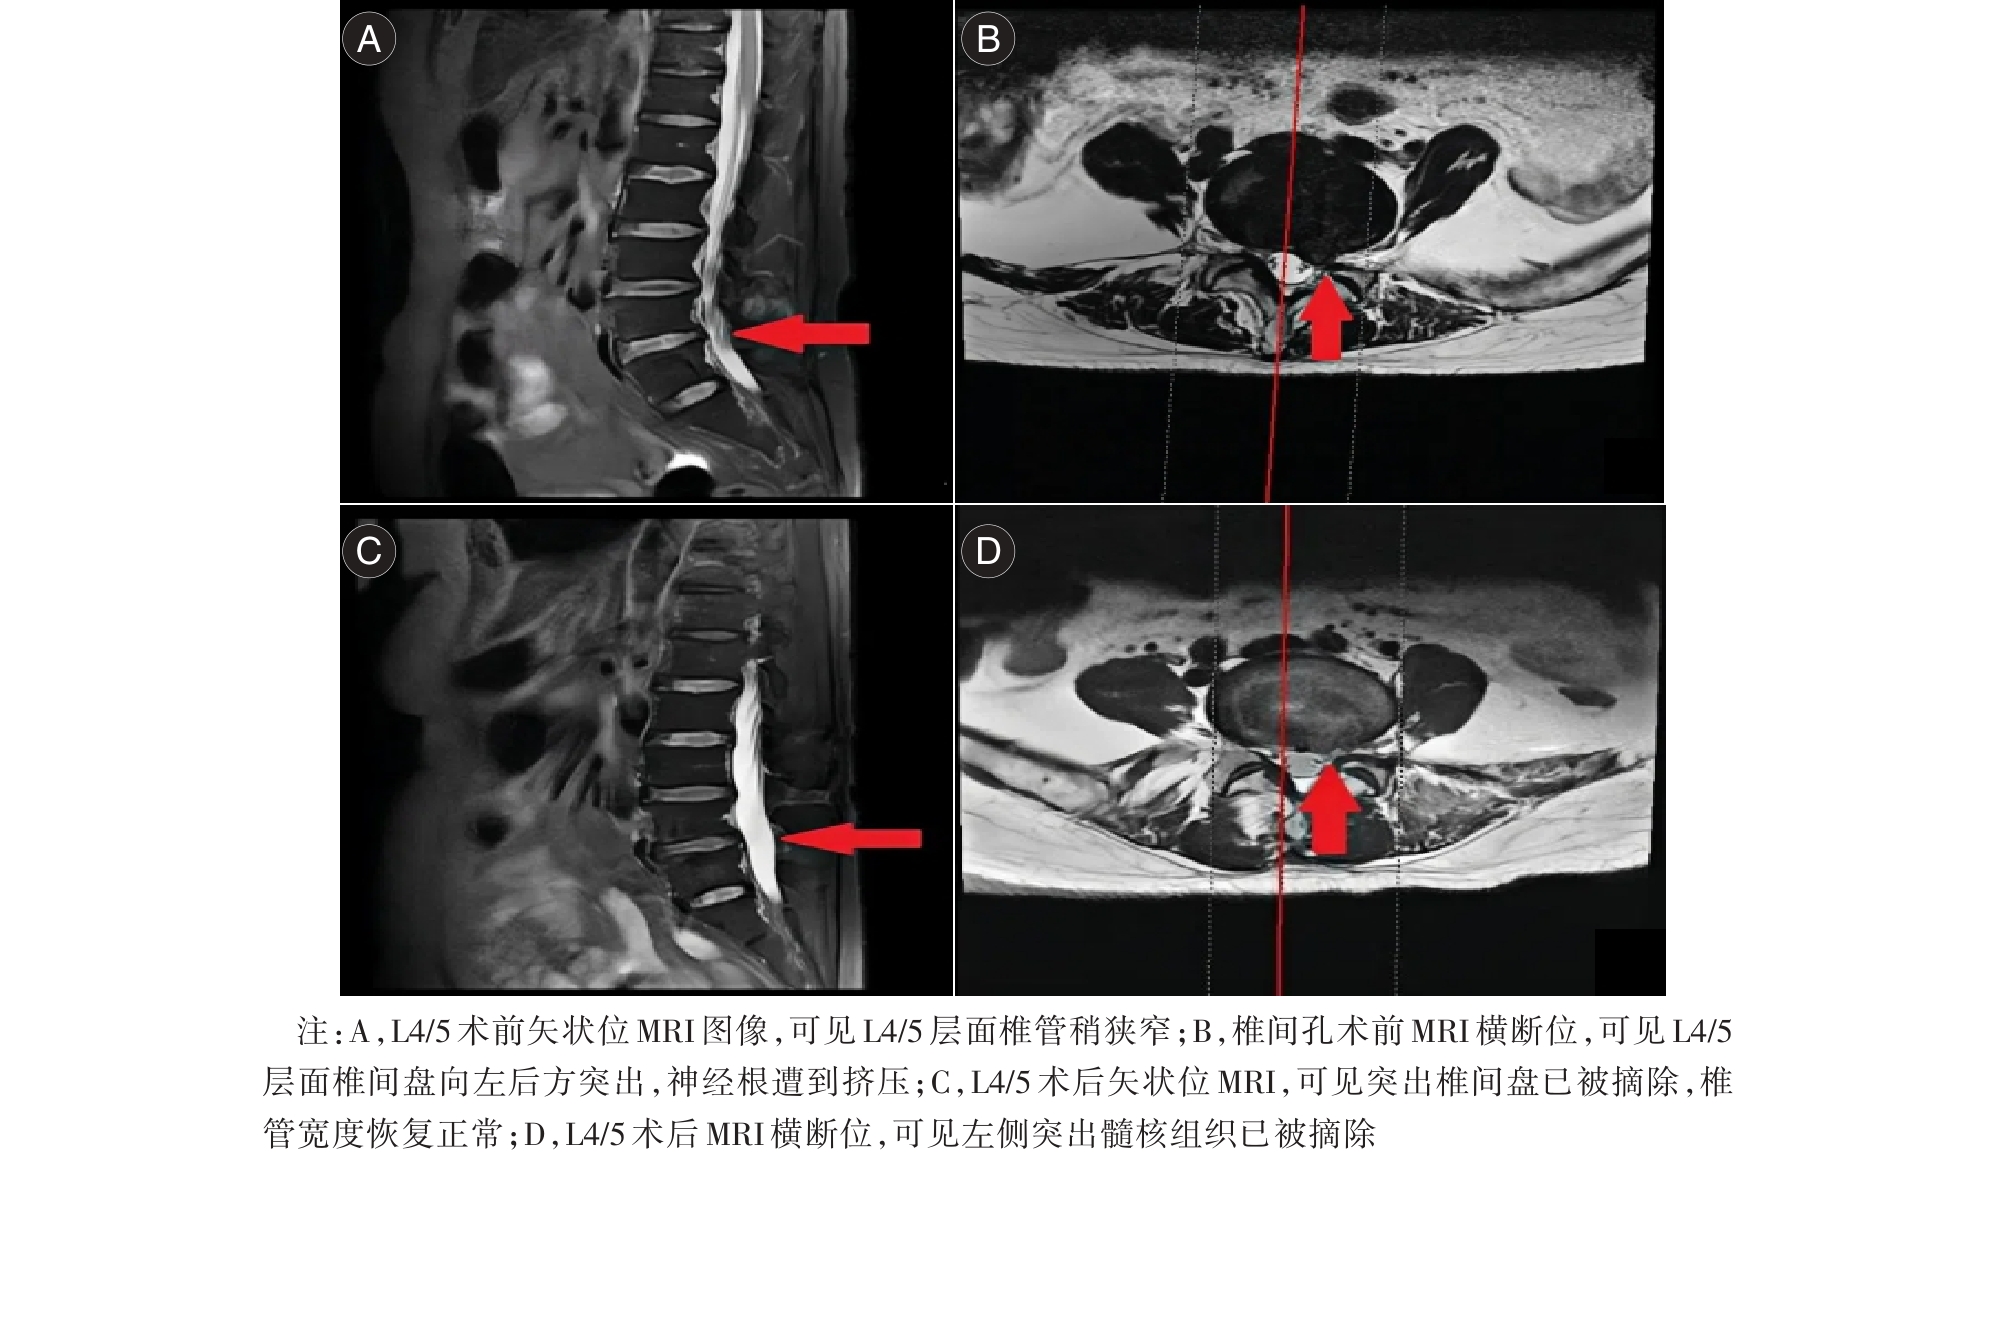

目的 分析经Kambin三角入路与经后方椎板间隙入路脊柱内镜手术对腰椎间盘突出症(LDH)伴侧隐窝狭窄患者的影响。 方法 选取152例LDH伴侧隐窝狭窄患者,按照手术入路方式分为Kambin组(n = 77)与椎板间隙组(n = 75),两组分别经Kambin三角入路、经后方椎板间隙入路。对比两组手术相关指标、视觉模拟评分法(VAS)、Oswestry功能障碍指数(ODI)评分、侧隐窝狭窄面积、并发症发生率。 结果 Kambin组手术时间及术后住院时间均短于椎板间隙组(P < 0.05);Kambin组术后1 d、1个月的VAS评分均低于椎板间隙组(P < 0.05);两组术后1、3个月的ODI评分比较无明显差异(P > 0.05);两组术后侧隐窝狭窄面积比较无明显差异(P > 0.05)。椎板间隙组出现1例术后感染。 结论 Kambin入路手术时间更短,两种入路均有效改善功能、扩大侧隐窝,椎板间隙入路需优化减少并发症。

Objective To evaluate and compare the effects of endoscopic spinal surgery performed via the Kambin's triangle approach and the posterior interlaminar approach on patients diagnosed with lumbar disc herniation (LDH) and concurrent lateral recess stenosis. Methods The clinical data of patients who underwent lumbar pedicle screw fixation at our hospital between January 2017 and December 2023 were retrospectively analyzed. Patient information including sex, age, diagnosis, surgical level, presence and type of postoperative neurological complications was recorded. Based on postoperative CT scans, the zone and grade of screw penetration were assessed, and the distribution of different types of pedicle screw penetration was documented. The association between specific types of pedicle screw penetration and the occurrence of postoperative neurological symptoms was then analyzed. Results The operation time and postoperative hospital stay in the Kambin group were significantly shorter than those in the interlaminar group (P < 0.05). On postoperative day 1 and at 1 month postoperatively, the VAS scores in the Kambin group were significantly lower than those in the interlaminar group (P < 0.05). No significant differences were observed between the two groups in terms of ODI scores on postoperative day 1 and at 3 months postoperatively, or in the postoperative area of lateral recess stenosis (P > 0.05). One case of postoperative infection was reported in the interlaminar group. Conclusions For patients with LDH and lateral recess stenosis, endoscopic spinal surgery via the Kambin's triangle approach is associated with a shorter operative duration. Both the Kambin's triangle approach and the interlaminar approach can effectively improve functional outcomes and decompress the lateral recess. However, the interlaminar approach requires further optimization to minimize the risk of complications.